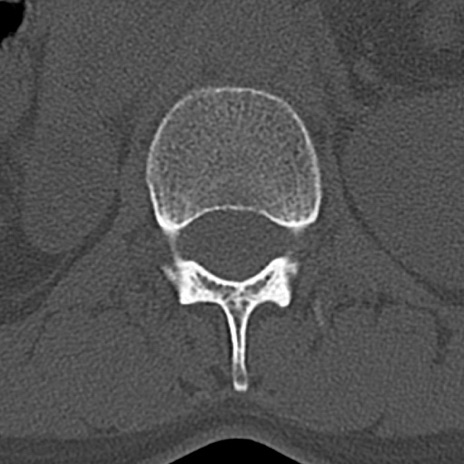

腰椎CT

横断像と矢状断像